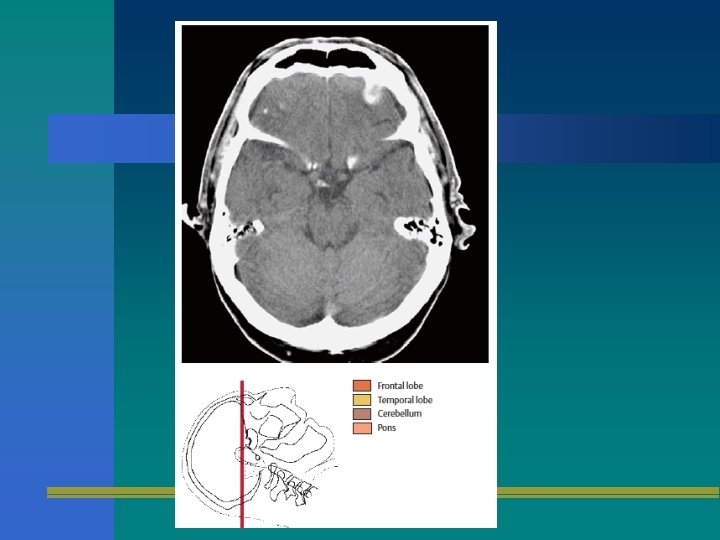

TOMOGRAFIA AXIAL

TAC